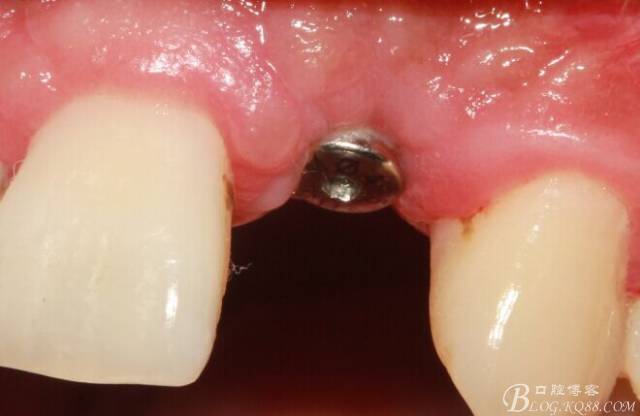

術(shù)后1個(gè)月

術(shù)后5個(gè)月